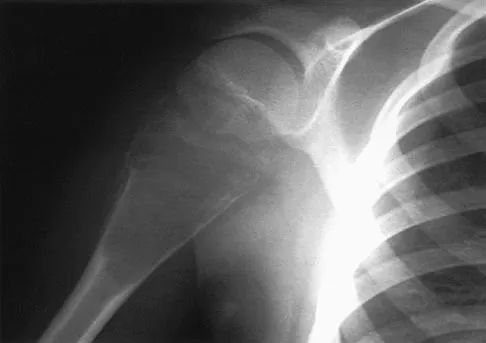

A 64-year-old man who was involved in a high-speed motor vehicle accident 6 weeks ago has been in the ICU with a closed head injury. Examination reveals that his range of motion for external rotation to the side is -30 degrees. Radiographs are shown in Figures 28a and 28b. What is the most likely diagnosis?